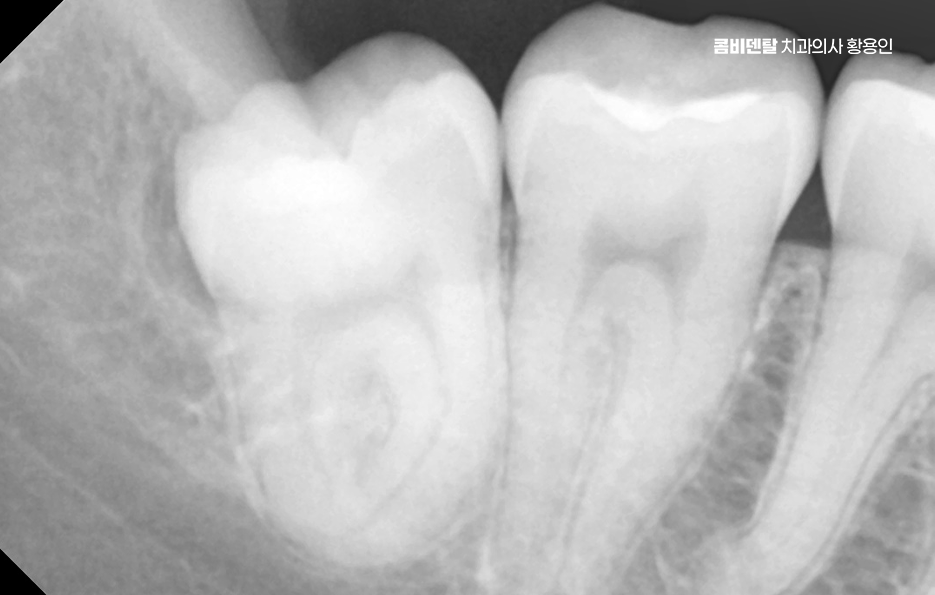

사랑니가 맹출하는 방향도 문제인데 수평으로 누워 있거나, 비스듬히 자라는 경우가 많다보니 이렇게 되면 앞쪽 어금니에 대한 압박을 계속 주다 보면 뿌리 쪽에 흡수가 생기거나, 치아 사이에 깊은 충치가 생기기도 해서 겉으로는 안 보이는데 내부에서부터 썩어 들어가는 경우가 많기 때문에, 이미 증상이 생겼을 때는 치료가 늦는 경우도 많이 있었어요

어금니는 구조상 씹는 힘을 가장 많이 받는 부위로 충격에 의한 마모, 균열, 손상이 잘 생기는 편이고 특히 충치가 생기면 빠르게 진행되는 경우가 많은데 어금니는 홈이 깊고, 작은 틈새에 음식물이 잘 끼는 구조여서 양치질을 아무리 열심히 해도 깨끗하게 닦는 게 어려울 수 있어요.

어금니 충치나 손상 또한 조기 치료가 중요하며 작은 충치는 레진으로 빠르게 막아주면 되지만, 벌써 충치가 크고 깊어졌다면 인레이나 크라운 같은 보철치료가 필요하겠고 특히 신경까지 손상이 갔다면 신경치료 후 크라운까지 진행해야 하며 치료가 늦어지면 결국 발치를 후 임플란트로 넘어가기 때문에 조기 치료와 정기적인 검진의 중요성을 평소 잘 알고 실천하는 것이 중요할 수 있었어요